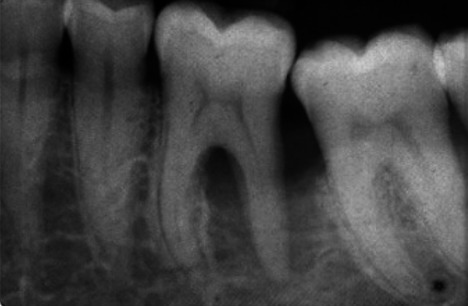

Abstract Image